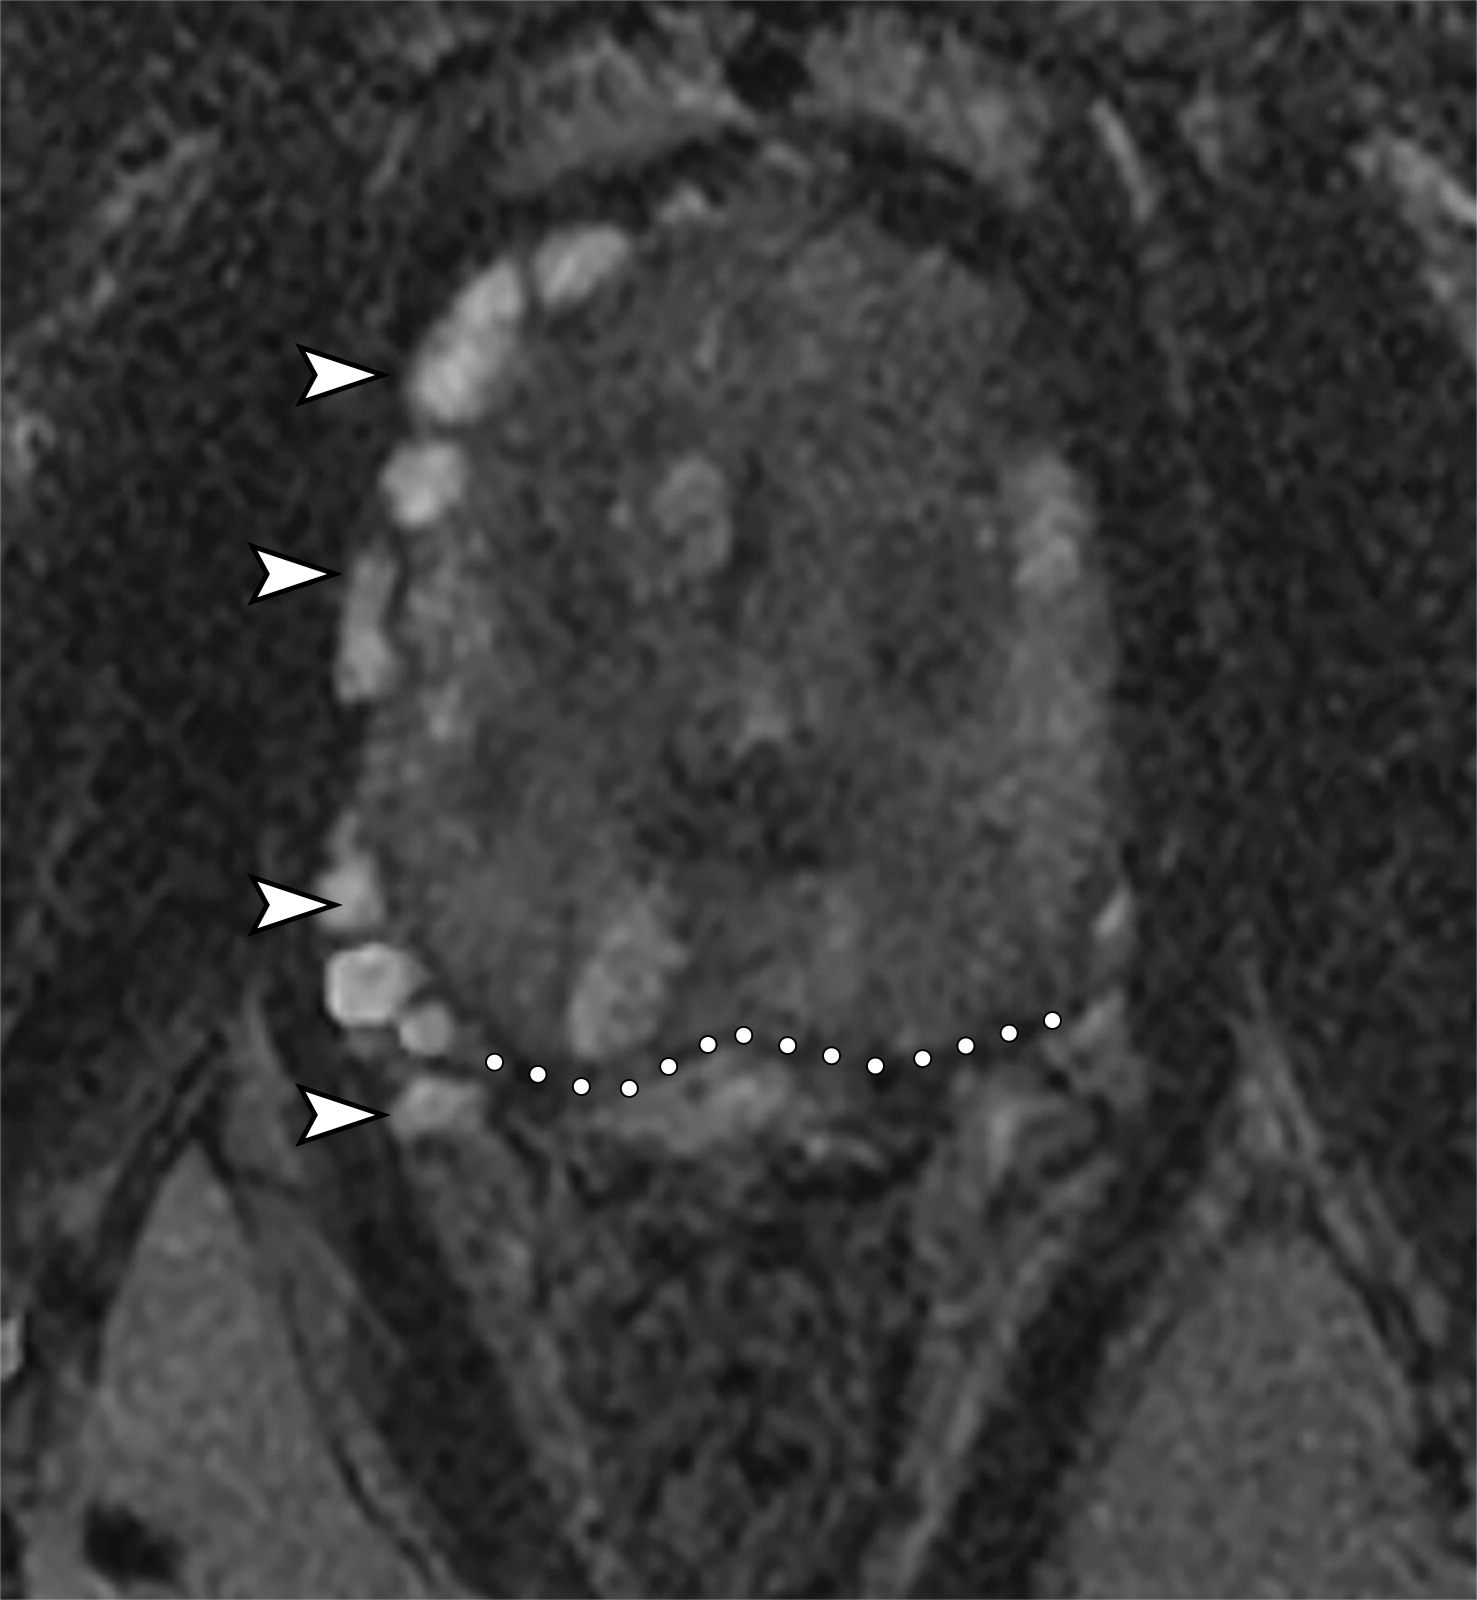

50岁以上男性骨盆和盆底的MRI解剖。

提肛肌(LA),由耻骨直肠肌(PR)、耻骨尾骨肌(PC)和髂尾骨肌(IC)组成;尾骨肌(C),前列腺(P),闭孔内肌(OI),会阴浅横肌(STP),球海绵体肌 (B), 坐骨海绵体肌(ISC),肛门外括约肌(EAS),肛门内括约肌(IAS),直肠(R),尿道括约肌(SU),也称为尿道外括约肌(U),它包围着整个膜性尿道。6774449af17bb1b8df6e83ab4e9fa158.jpeg